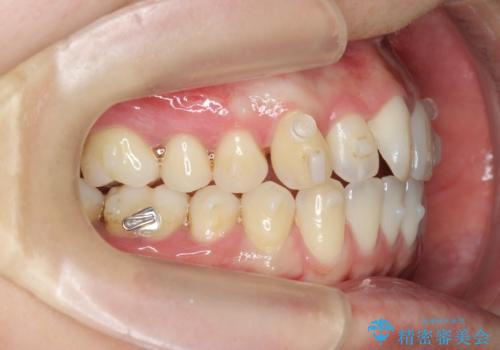

前歯のねじれを改善 マウスピース矯正インビザライン

- 目立つ前歯のねじれを改善したい、と矯正治療を希望され来院されました。

マウスピース矯正インビザラインを用いて綿密に治療計画を練り、美しい歯並びを手に入れるべく治療計画を立案します。

左側の奥歯は後方移動を行うことで、理想的な噛み合わせに整えるとともに、前歯の突出感も同時に改善することができました。